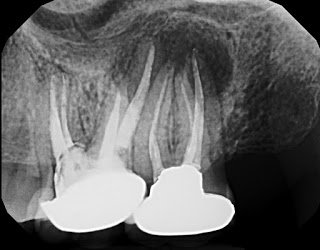

Here is the preoperative radiograph again:

History: This patient has had symptoms on and off in the upper left for six years. She cannot chew comfortably on this side and feels a constant pressure in the area. She cannot walk up stairs without feeling dull pain in the area. The original treatment on #14 was performed in 2006 or 2007. Tooth #14 was then retreated by an endodontist in 2009, followed by persistent symptoms, and then treatment of tooth #15 soon after. With retreatment of #14 and treatment of #15, her symptoms improved for a short time, but soon returned.

Radiographic Exam: Large radiolucency centered on #15 but overlapping the distal of #14. Widened PDL mesial #14. 3 canals obturated #15. Large, possibly strip perforated, canal preparation in the middle and cervical third of both #14 and #15, possibly compromising root strength.